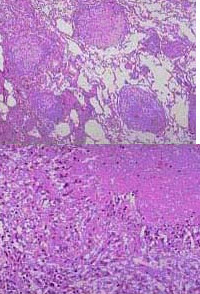

23、单项选择题

仔细观察所给的“慢性浅表性胃炎”不同放大倍数之镜下观,

该种细胞常见于下列哪种炎症()

死者,女性,2岁。腹痛、腹泻、里急后重2天,加剧3天伴高热,抽搐。死后尸检。

该疾病多发生于机体哪个部位()

A.食道下段

91、单项选择题

患者女性,56岁,上腹部隐痛并向右肩背放射。既往有多次胆绞痛史。手术切除胆囊,术后巨检胆囊增大,内含结石2枚,直径1.5cm,黏膜粗糙,并可见多个黄色小息肉样物,易脱落。壁厚0.3cm。

镜检如图所示,最佳诊断为()

121、单项选择题

息肉内泡沫样细胞属于哪一类细胞()